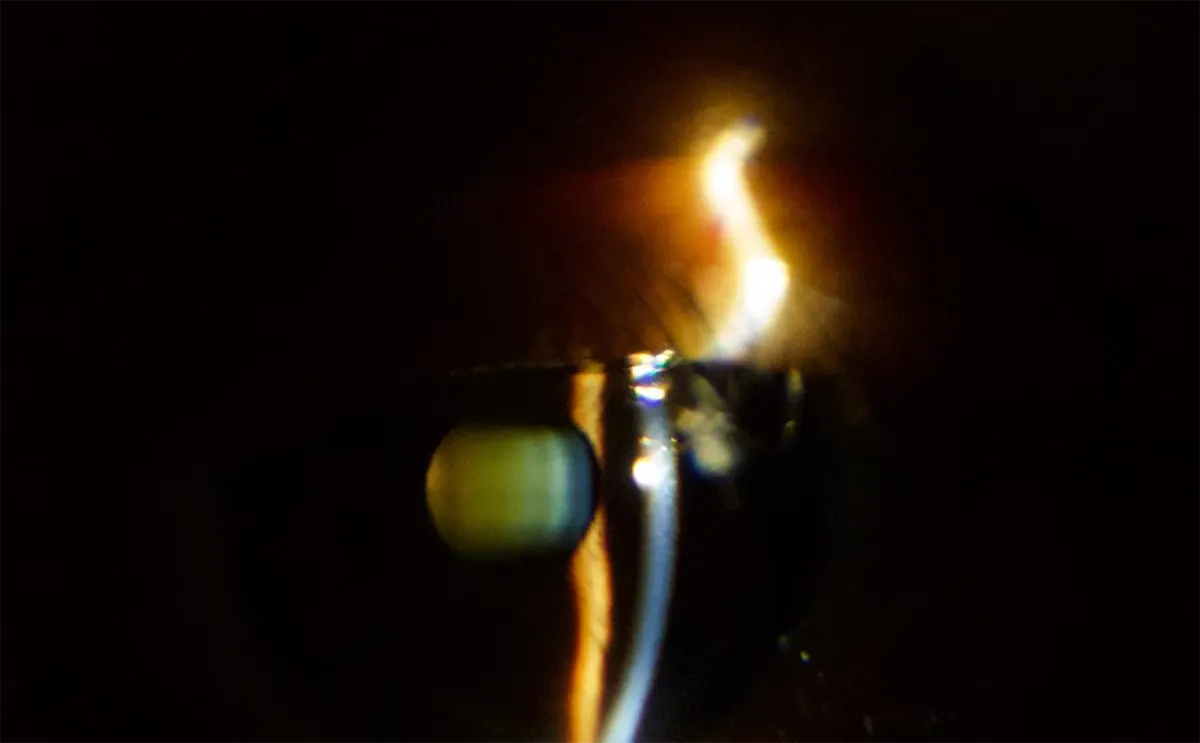

- Imágenes capturadas con la lámpara de hendidura portátil PSL-D20: Estas son imágenes de rendija y difusa capturadas con un PSL-D20. La luz difusa de múltiples colores y el control de intensidad facilitan la captura de imágenes de alta calidad.

Imágenes capturadas con PSL-D20

Estas son imágenes de rendija y difusa capturadas con un PSL-D20. La luz difusa de múltiples colores y el control de intensidad facilitan la captura de imágenes de alta calidad.